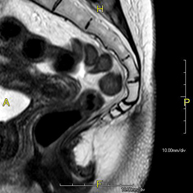

Prova diagnòstica no invasiva que consisteix en l'obtenció d'imatges d'alta definició anatòmica de l'abdomen mitjançant l'ús d'un camp electromagnètic i ones de ràdio (amb un emissor i un receptor). No utilitza radiació ionitzant. En aquesta exploració s'inclouen el fetge, el pàncrees, la melsa, la via biliar, la vesícula biliar, les glàndules suprarenals, els ronyons, l'aorta abdominal, la vena cava inferior, l'estómac, el duodè, etc. En alguns casos caldrà emprar contrast paramagnètic (Gadolini) per caracteritzar les lesions. - RM Pelvis femenina

Prova diagnòstica no invasiva que consisteix en l'obtenció d'imatges d'alta definició anatòmica de la pelvis mitjançant l'ús d'un camp electromagnètic i ones de ràdio (amb un emissor i un receptor). No utilitza radiació ionitzant. Es realitza per a l'estudi de patologies d'úter, d'ovari, de trompes i de vagina, ja siguin d'origen tumoral, inflamatori o vascular. També permet valorar les estructures adjacents localitzades a la pelvis i la identificació de les seves alteracions. De vegades és necessari l'ús de contrast intravenós (Gadolini) per caracteritzar les lesions. - RM Pelvis masculina

Prova diagnòstica no invasiva que consisteix en l'obtenció d'imatges d'alta definició anatòmica de la pelvis masculina mitjançant l'ús d'un camp electromagnètic i ones de ràdio (amb un emissor i un receptor). No utilitza radiació ionitzant. No requereix preparació prèvia. En algunes ocasions necessita l'ús de contrast paramagnètic (Gadolini) per caracteritzar les lesions. Aquesta prova permet valorar òrgans com la bufeta urinària, la unió entre els urèters i la bufeta, la pròstata, les vesícules seminals, la uretra i els ossos de la pelvis, entre d'altres. - RM de Fetge